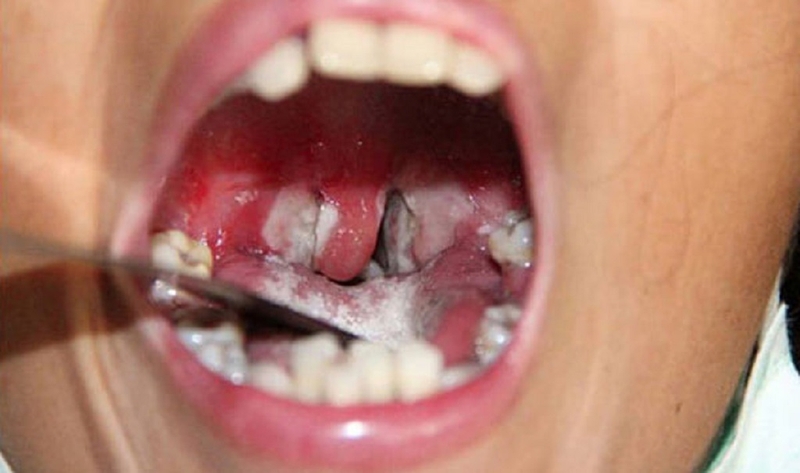

Để phân biệt bạch hầu và viêm họng thì trước tiên bạn cần nhận biết được các triệu chứng cơ bản nhất của bệnh bạch hầu. Triệu chứng của bệnh bạch hầu thường xuất hiện từ 2 đến 5 ngày sau khi người nhiễm vi khuẩn. Ban đầu, những triệu chứng này có vẻ giống với viêm họng hay cảm lạnh thông thường. Sau 3 - 7 ngày quan sát, bệnh nhân thường phát hiện một lớp màng dày, có màu trắng đục hoặc xám xuất hiện tại cổ họng hoặc amidan.

Phân biệt bạch hầu và viêm họng qua giả mạc. Đây là một trong những triệu chứng đặc trưng của bạch hầu. Giả mạc của bệnh nhân bạch hầu xuất hiện dày và bám chặt vào niêm mạc họng, gần như không tách ra được, nếu cố gắng tách sẽ bị chảy máu. Ngược lại, giả mạc ở bệnh nhân viêm họng mỏng, dễ dàng lấy ra mà không gây chảy máu và không có màu sắc sẫm như bạch hầu.